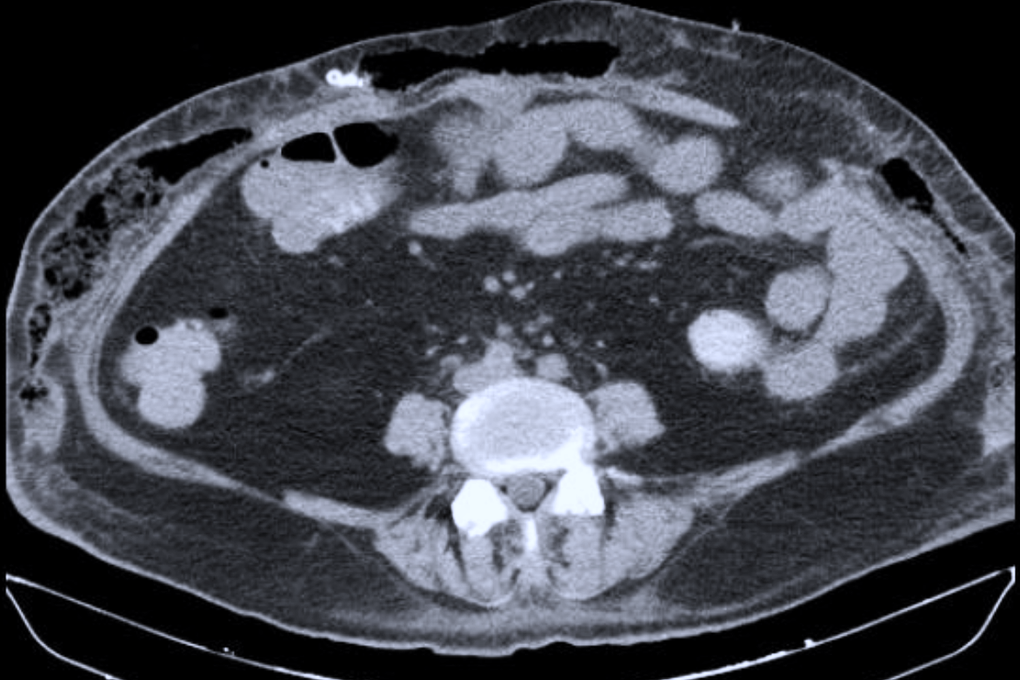

Chiều 3/12, BSCKII Nguyễn Văn Tiến, Trưởng khoa Ngoại Phụ khoa, Bệnh viện Ung bướu TPHCM, cho biết ông cùng các cộng sự vừa phẫu thuật cho một bệnh nhân mang khối u khổng lồ, khiến bụng to như ễnh ương.Bệnh nhân là cô gái 20 tuổi tên B. (ngụ TPHCM), sinh viên đại học năm thứ 3. Theo bệnh sử, cách đây gần 1 năm cô thấy bụng to dần, đến 6 tháng nay thì tốc độ gia tăng kích thước nhanh hơn.Một phần tưởng mình mập (bệnh nhân nặng gần 80kg), phần mặc cảm vì sợ bị cười chê và hiểu lầm, bệnh nhân che g...